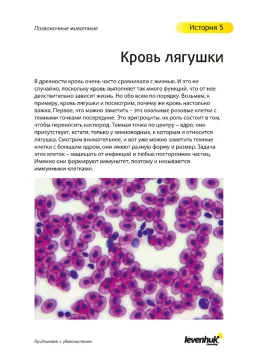

72 Blood Smear Fish Клетки крови рыбы